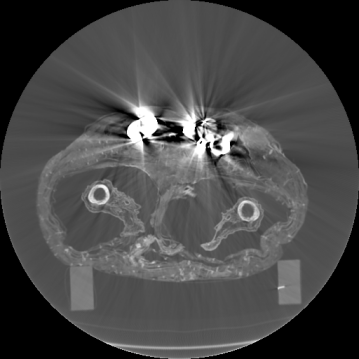

Figure 3: Visualization of axial frames of a mummy [6] selected in proximity of the thigh. (a) Some of the regions we are interested to segment are indicated. (b) Artifacts caused by presence of metals.

In Fig. 3a, we show one axial slice of a male mummy with indication of the regions to be segmented. Fig. 3b illustrates that metals present inside a bandaged mummy generate severe artifacts, which are not present in standard biomedical data.